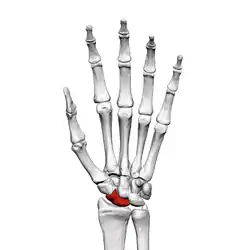

Left hand anterior view (palmar view). Scaphoid bone shown in red.

The scaphoid bone is one of the carpal bones of the wrist. It is situated between the hand and forearm on the thumb side of the wrist (also called the lateral or radial side). It forms the radial border of the carpal tunnel. The scaphoid bone is the largest bone of the proximal row of wrist bones, its long axis being from above downward, lateralward, and forward. It is approximately the size and shape of a medium cashew nut.